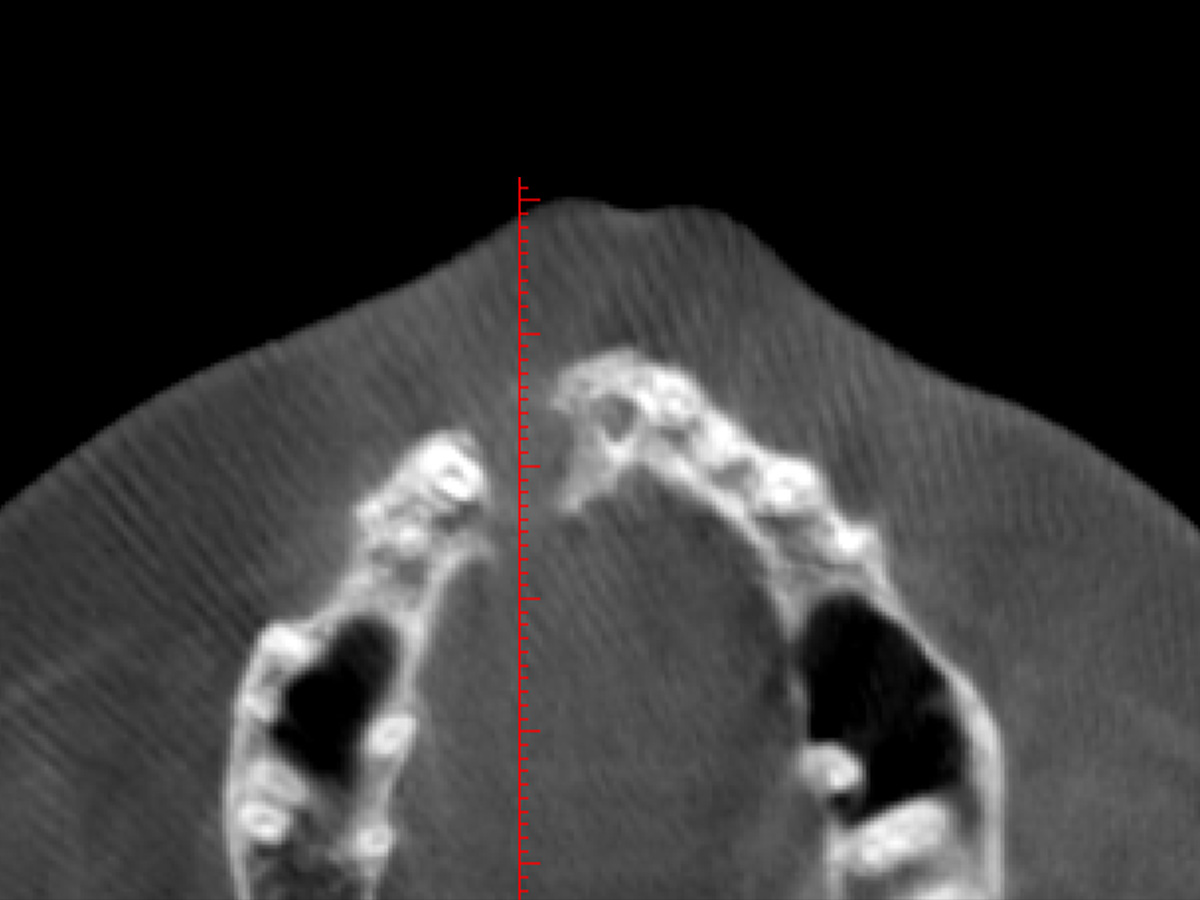

Abbildung 5

Im DVT ist eine große zystische Formation unter Einschluss der Wurzeln 11 und 12, die vom Canalis nasopalatinus...

Abbildung 6

...bis mesial 13 mit einer kleineren Perforation zum Nasenboden...

Abbildung 7

...und größeren Perforationen nach vestibulär und palatinal reicht.

Nach einem Zahntrauma im Jugendalter mit anschließender endodontischer Versorgung stellte sich unsere 24-jährige Patientin mit seit einigen Monaten bestehendem, rezidivierendem Druckgefühl und leichten Schmerzen in regio 11 und 12 vor (Abb. 1, 2, 3). Die klinische Untersuchung ergab an Zahn 11 und 12 Lockerungsgrad 1 und, wie zu erwarten, eine negative Sensitivität. Es lag ein leichter Perkussionsschmerz vertikal wie horizontal vor. Die Krone auf Position 11 zeigte eine leichte Verfärbung im Vergleich zu den Nachbarzähnen. Ein OPG ergab eine – in ihrer Ausdehnung nicht sicher zu beurteilende – Aufhellung im Knochenbereich regio 11 und 12 (Abb. 4). Als Nebenbefund waren teilretinierte Zähne 38 und 48 sowie ein vollständig retinierter Zahn 28 als Mikroform nachzuweisen. Ein zusätzlich durchgeführtes DVT zeigte eine große zystische Formation unter Einschluss der Wurzeln 11 und 12, die vom Canalis nasopalatinus bis mesial 13 mit einer kleineren Perforation zum Nasenboden und größeren Perforationen nach vestibulär und palatinal reichte (Abb. 5, 6, 7).